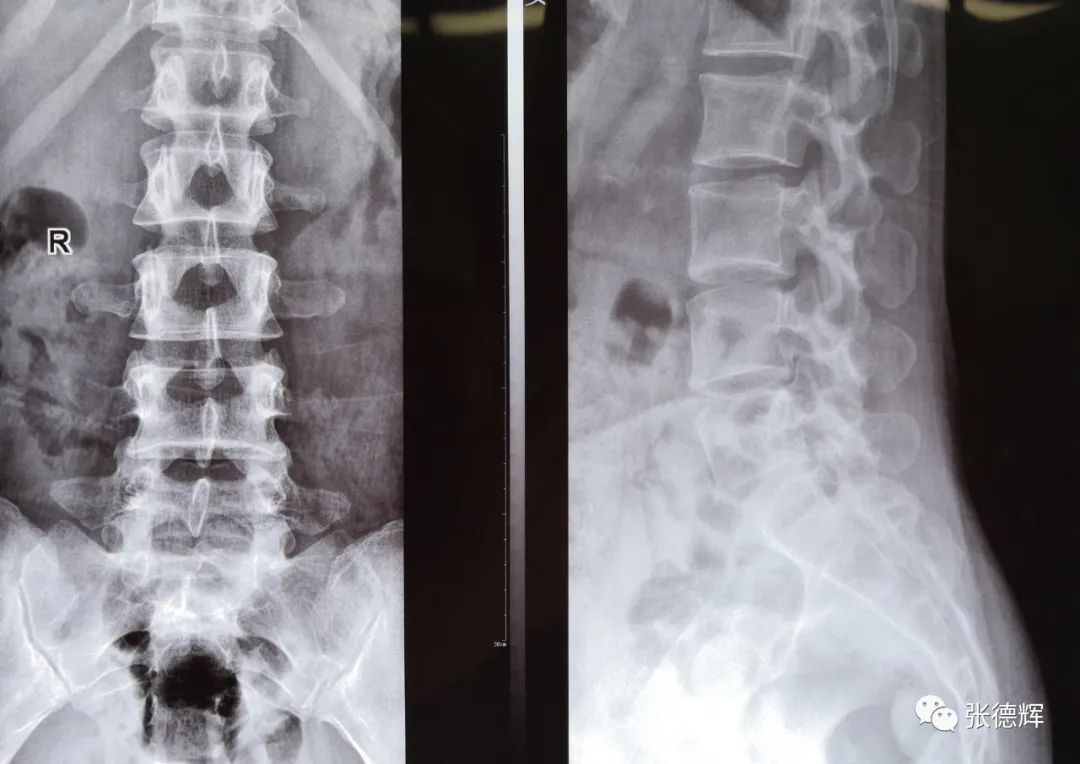

腰椎正侧位X光片未见骨结构异常